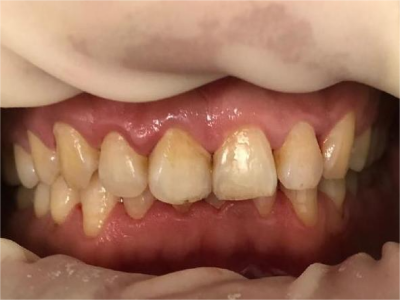

牙釉质发育不全牙表面上有坑图

牙釉质发育不全发展到严重时,导致牙釉质表面缺损,表现为带状、窝状的褐色凹坑,容易积存食物残渣诱发龋齿,表现为牙齿边上出现深褐色小洞。